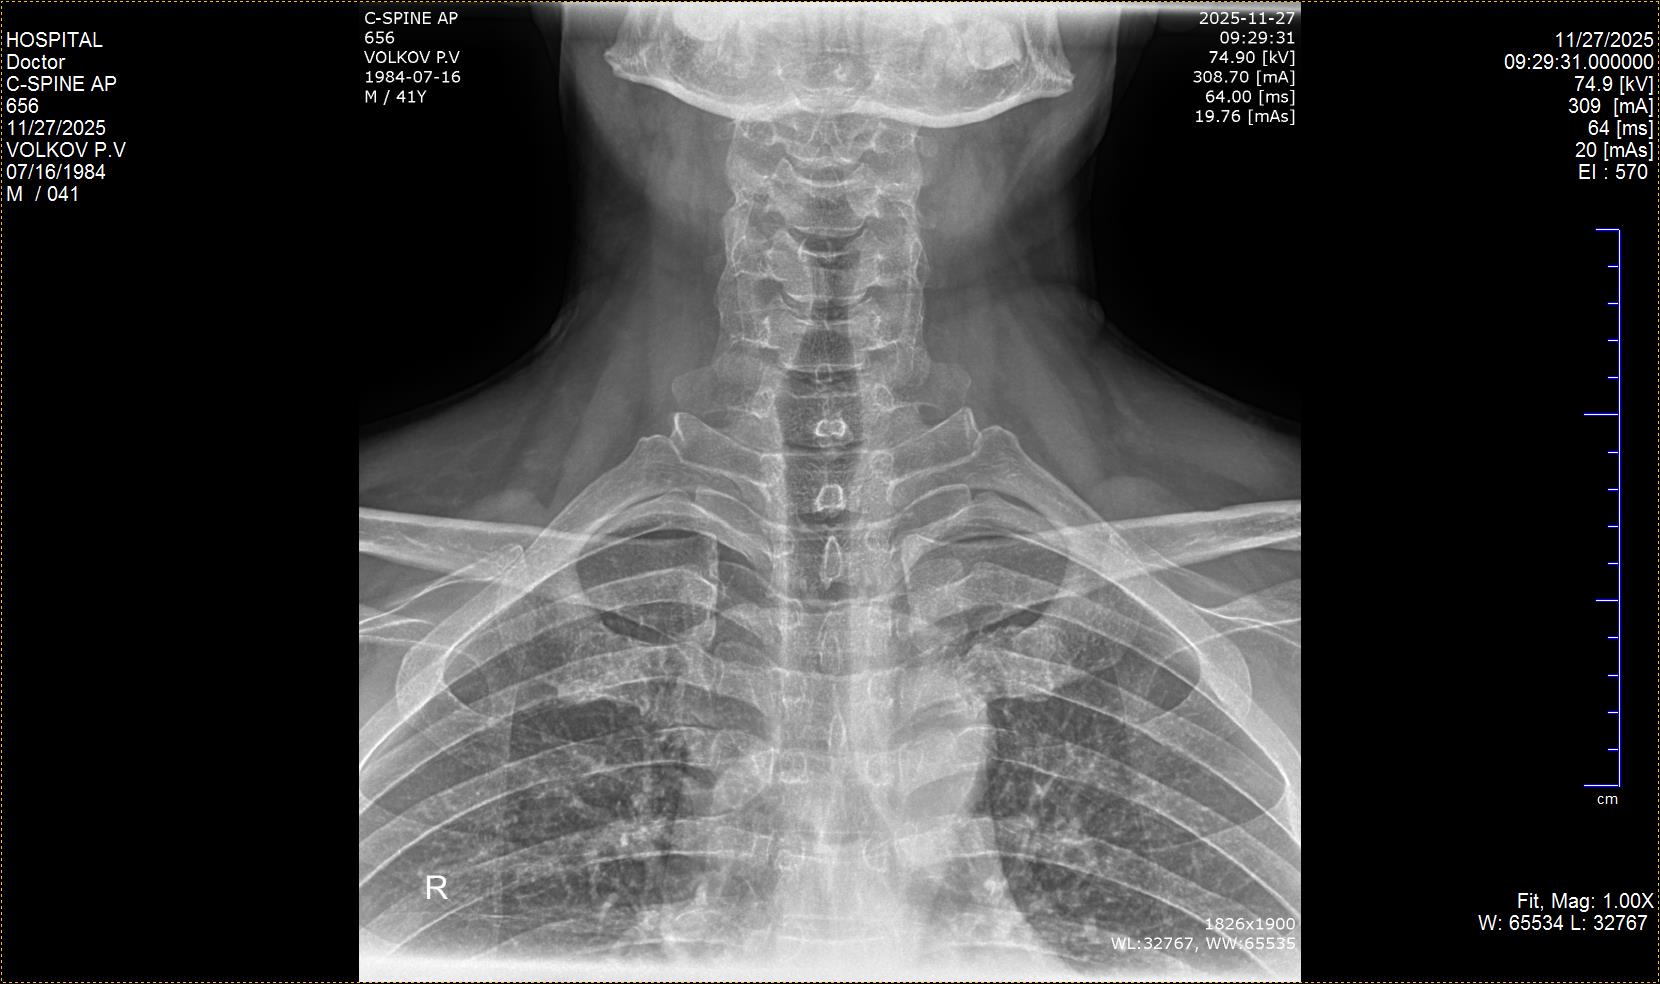

Помогите, пожалуйста, расшифровать снимки.  Не поворачивается голова вправо, при попытке  через силу мышцами её повернуть начинается боль слева и в затылочной части. Один врач  ставит остеохондроз, спондилоартроз. Второй просто остеохондроз и сколиоз 1 степени.  Третий: остеохондроз 2ст., спондилоартроз 1ст.

Одной из причин боли и ограничения движений у Вас может быть шилоподъязычный синдром. У Вас удлинённые шиловидные отростки. Для подтверждения/исключения потребуются консультации челюстно-лицевого хирурга, лор-врача и невроолога.